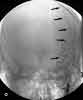

The initial CT scan of the brain showed a linear hyperdensity in the region of the left middle cerebral artery, which indicated thrombus formation (Figure 1). An area of cerebral edema was noted in the region with a small effacement from left to right. A cerebral angiogram performed 6 hours after the CT scan revealed a complete dissection of the left internal carotid artery (ICA) from the second cervical segment craniad (Figure 2). A follow-up CT brain scan 24 hours later demonstrated a large, left middle cerebral artery ischemic infarction with midline shifting and evidence of left uncal herniation (Figure 3).

Carotid dissection related to fibromuscular dysplasia is distinguished by a concentric narrowing of the lumen and may involve multiple arteries. Atherosclerotic arterial dissection usually occurs at the bifurcation and at the carotid siphon. Complete carotid stenosis of the distal branch of the middle cerebral artery (MCA) produces severe neurologic deficits. A hyperdense middle cerebral artery (HMCA) demonstrated in a noncontrast CT scan represents a thromboembolism and is associated with a large MCA ischemic infarction.6 A recent study showed that a hyperdense sylvian fissure MCA “dot sign” in patients with acute ischemic stroke is a more reliable early marker of thromboembolic stroke of the distal MCA branches than the HMCA sign.16